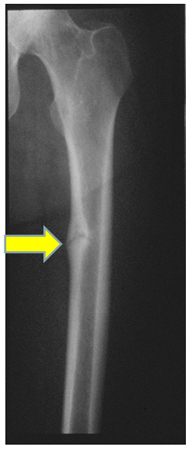

Radiograph of the femoral shaft in a patient with osteomalacia demonstrating a 'pseudofracture' (also known as Looser's zone) on the medial aspect of the mid-femoral shaft

From the collection of Bridget Sinnott, MD